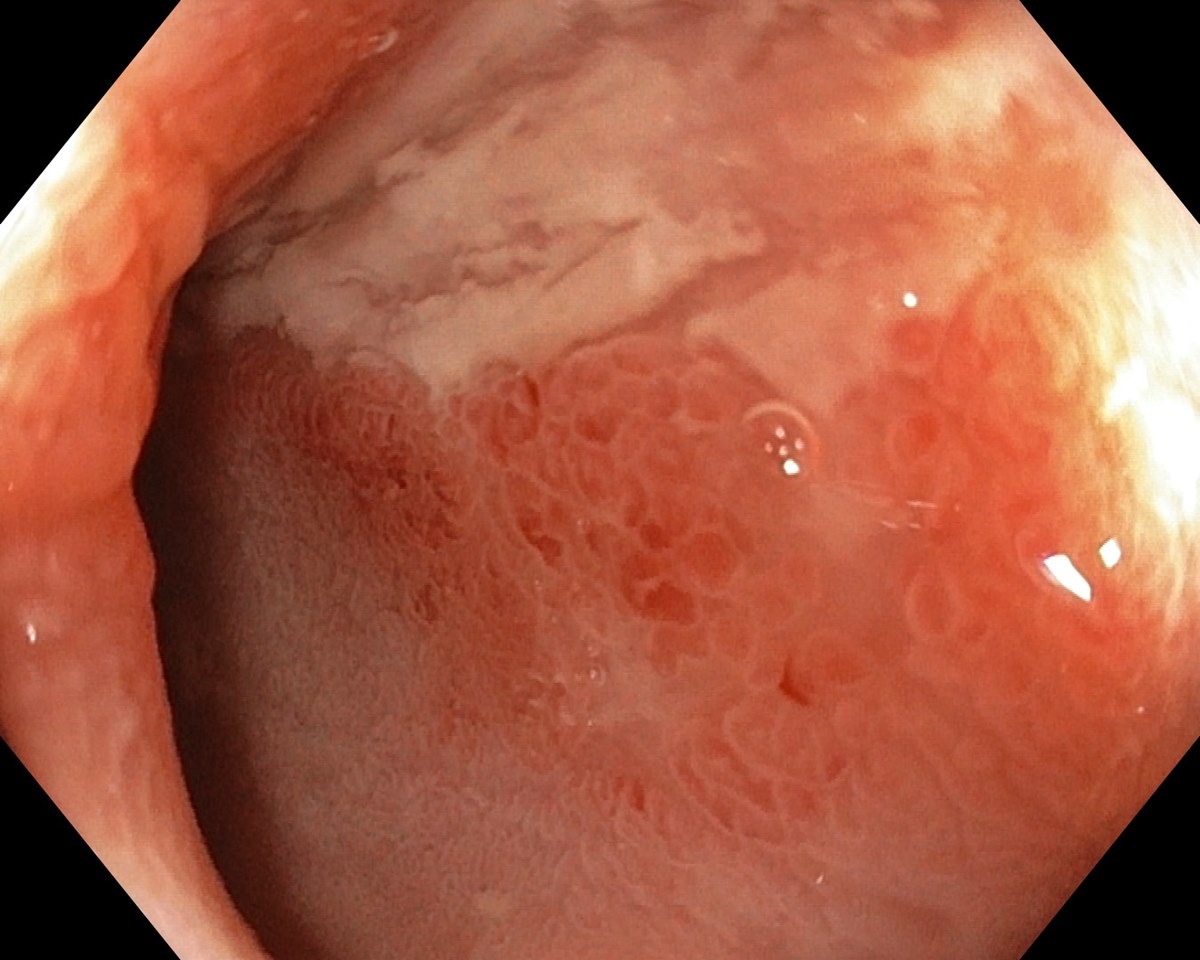

![]() Rectal Crohns Disease  |

Collage: Crohn´s Disease |